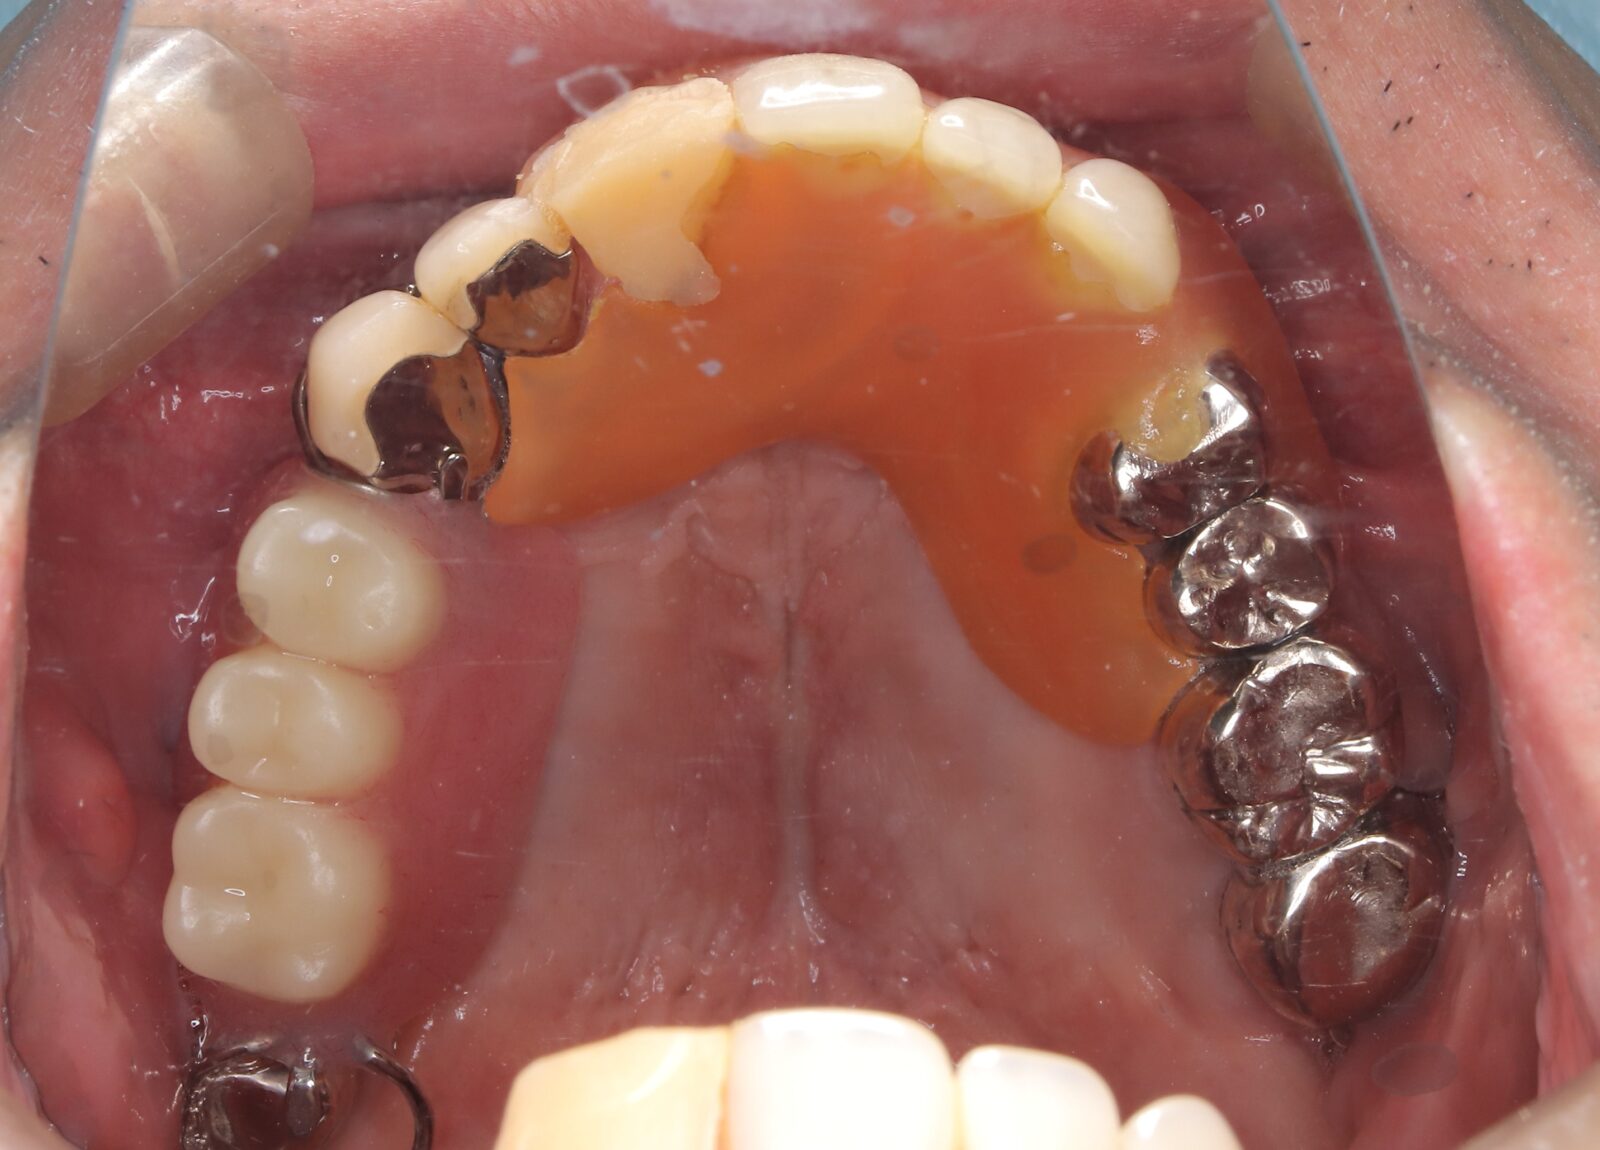

矯正と補綴が必要で実施した症例

左側に隙間。歯の数が少ない。もともと2番と7番がない。(先天欠如)歯の数が少ないため上顎のアーチ全体が小さい。歯槽骨の幅も狭く、歯肉も薄い。骨質も弱かった。

上顎左右2番と6番が先天欠如。下顎左右1番も先天欠如でもともとブリッジが装着されていた。

左右非対称なすきっ歯。上顎の前歯がないので左側の隙間を左右2番相当部に集めた。

上下の前歯が反対の噛み合わせ(受け口)で、干渉しているためうまく閉じることができず、奥歯は左右同時に噛めないので、どこかにずらさないと口を閉じられない。

左右の歯を同時に合わせることができず、どこで噛んだら良いかわからない噛み合わせでした。

小臼歯部は噛み合うことがない側方の開口状態。矯正と補綴が必要なケース。 主訴は顎の不調と歯軋り、夜間の食いしばり。

マルチブラケットとインビザラインを併用し、クラウンとブリッジを装着しました。

上顎左右2番は、歯が入るスペースを作り、ブリッジを装着しました。

他の歯医者で何軒も断られていました。 骨の幅がうすくインプラントはできない。骨の質も柔らかい。PCR検査の結果も歯周病ハイリスク患者でした。

歯の位置は、本人の顎が安定する場所を探して着地した。 左右で噛み合わせが非対称で、理想的な歯のポジションを獲得できなかったものの、左右同時に噛むことができるようになった。

顎関節の症状も落ち着いて、開口障害や、顎の痛みは無くなった。

矯正治療はどの装置を選択しても歯周病のリスクを高めてしまう。

これ以上の歯の移動が歯周病と骨質、骨の代謝のバランスの兼ね合いで困難であると判断し、ここが着地点とした。